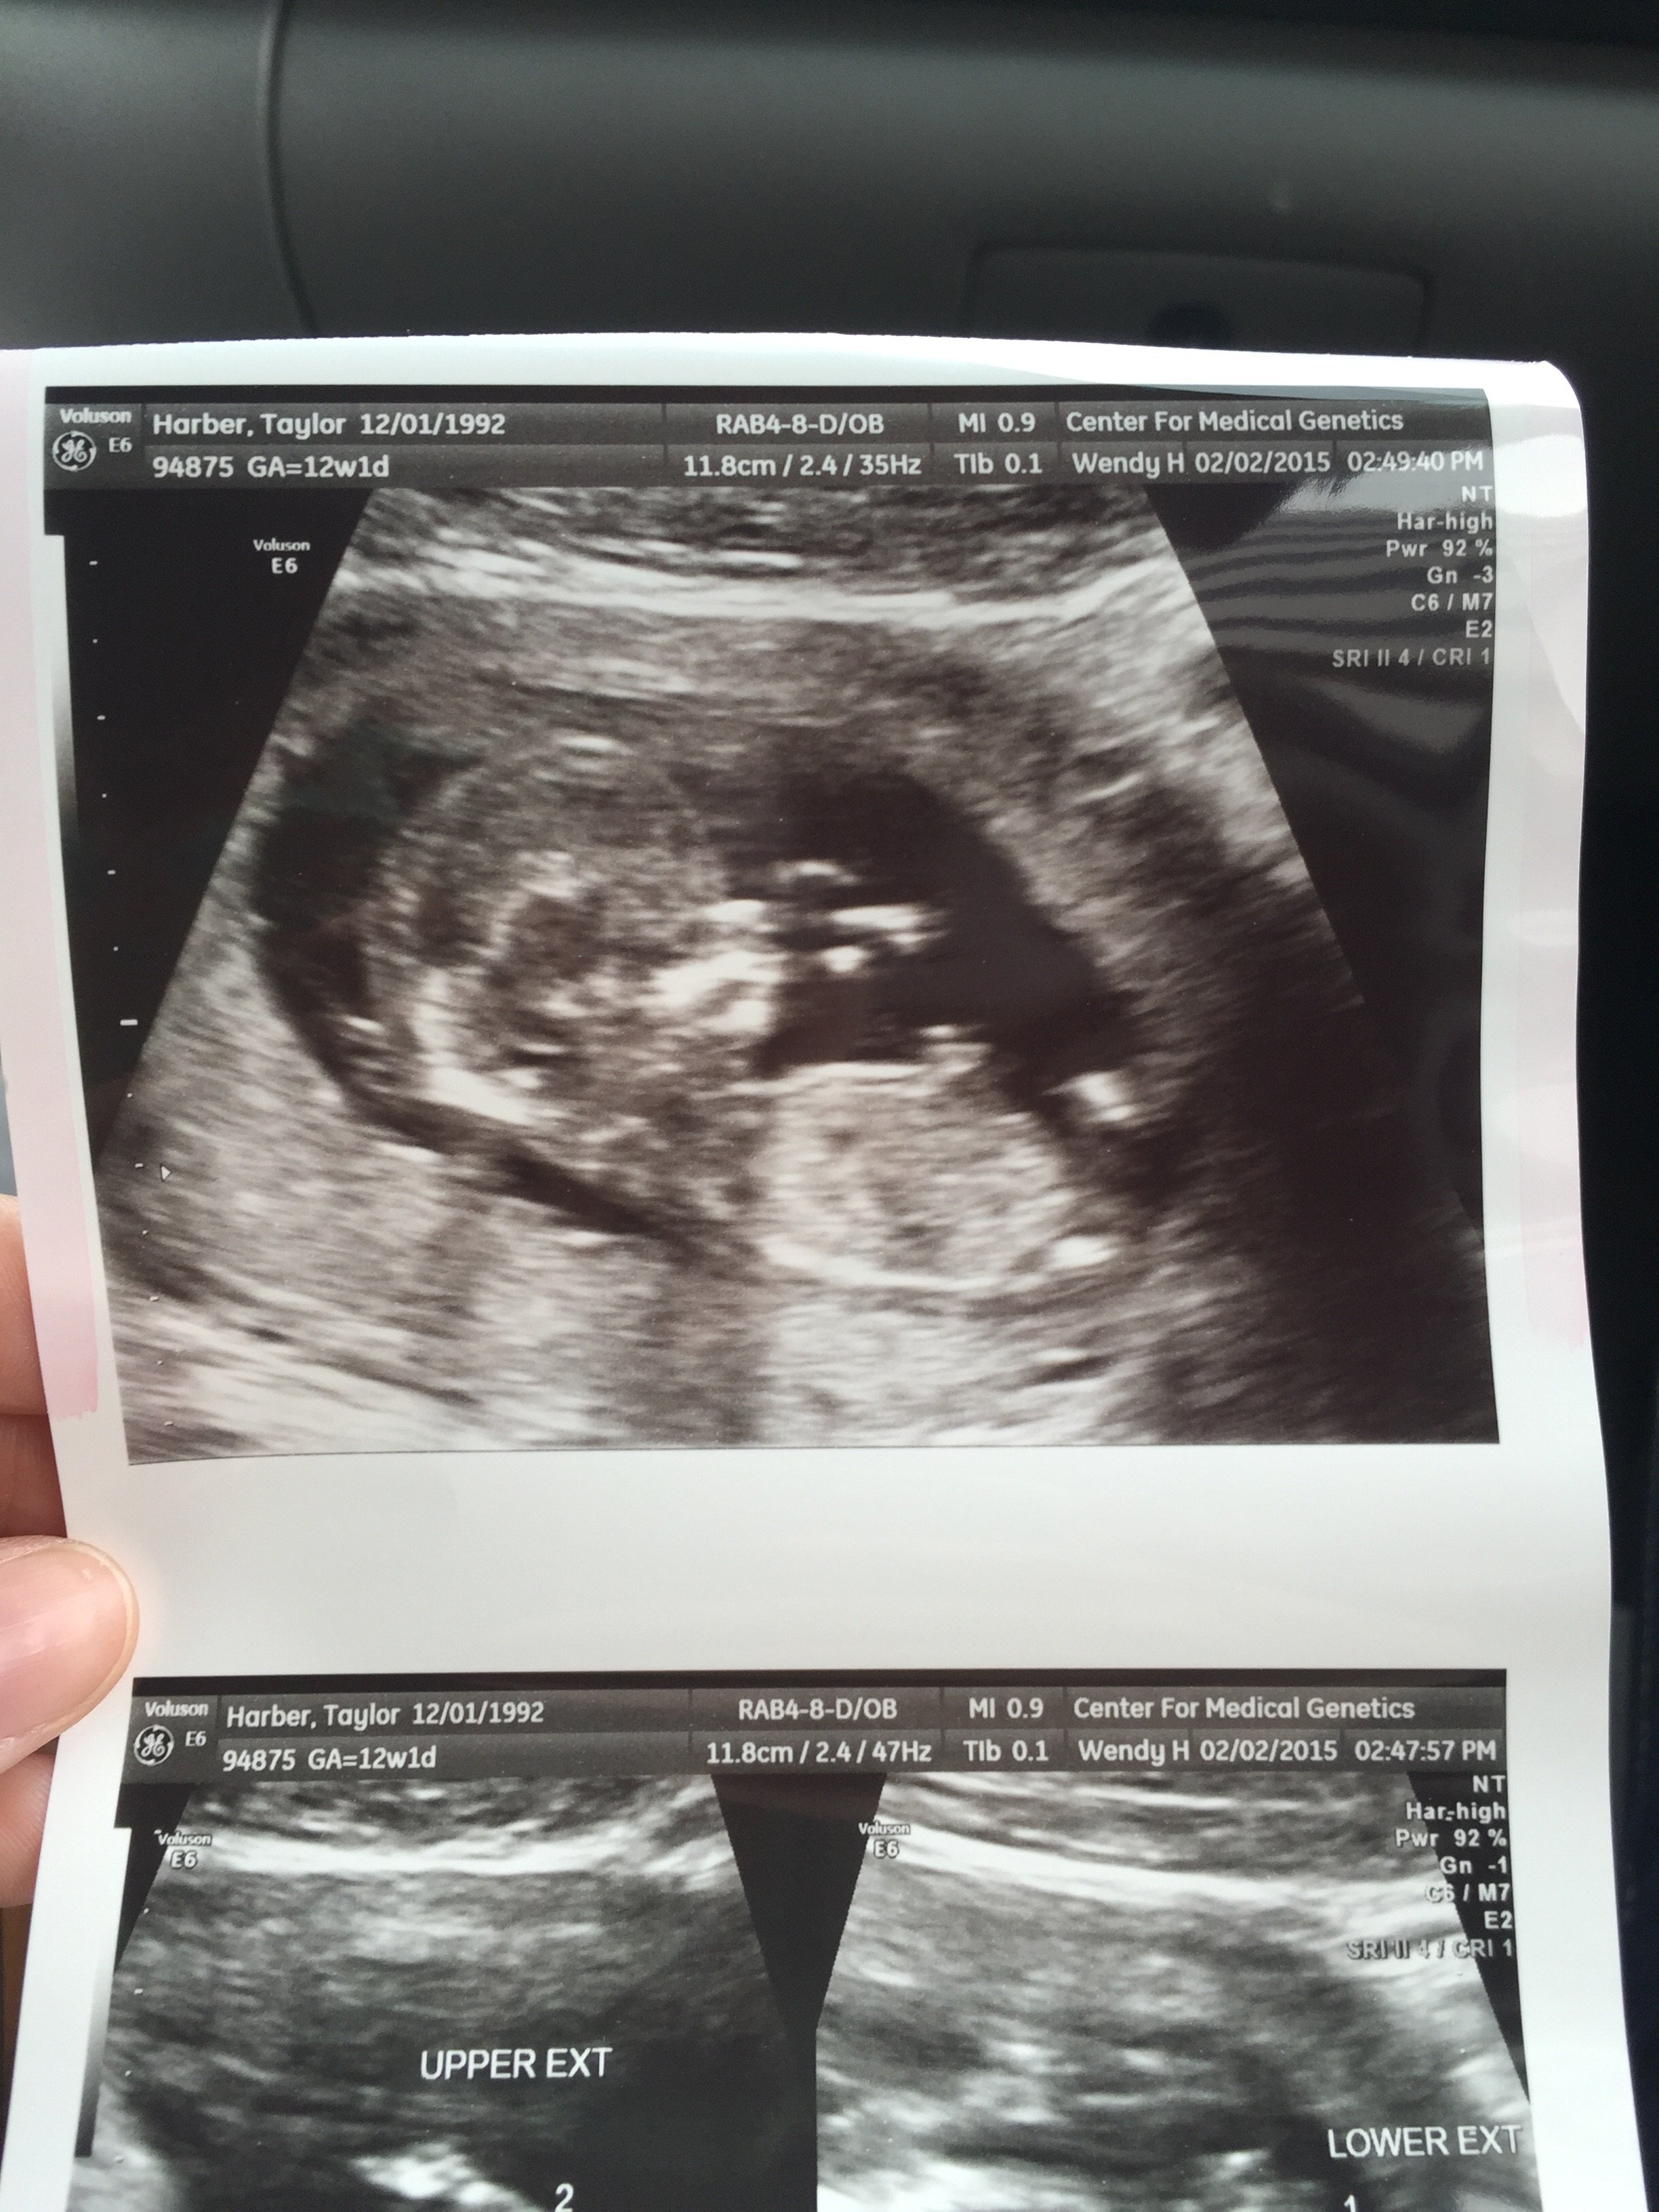

This is pretty interesting! According to this theory, a girl will have a more rounded forehead and a boy will have more of a slope forehead. This is my sonogram at 14 weeks. And the skull looks to be more sloped straight down then rounded and bulb like... but it's still too early to tell. What do you ladies think? And has anyone else ever looked into it?

when pregnant with my other kids, and have said "the profile just looks like a ___(insert boy/girl here____!" So this theory excites me and could definitely be plausible. I should dig out the albums and look to see if it holds true to my kids.